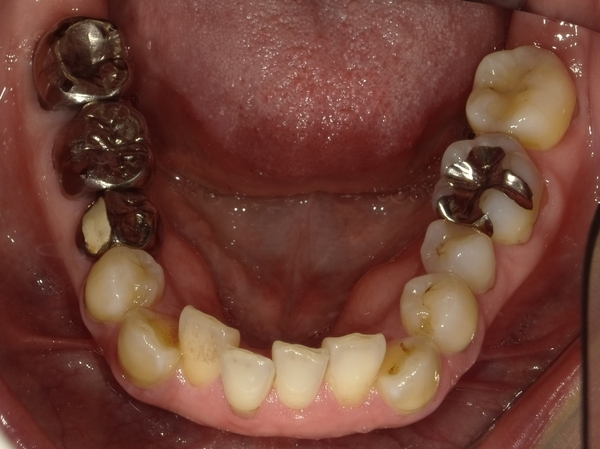

ガタガタとした歯並びや八重歯(叢生)CASE8